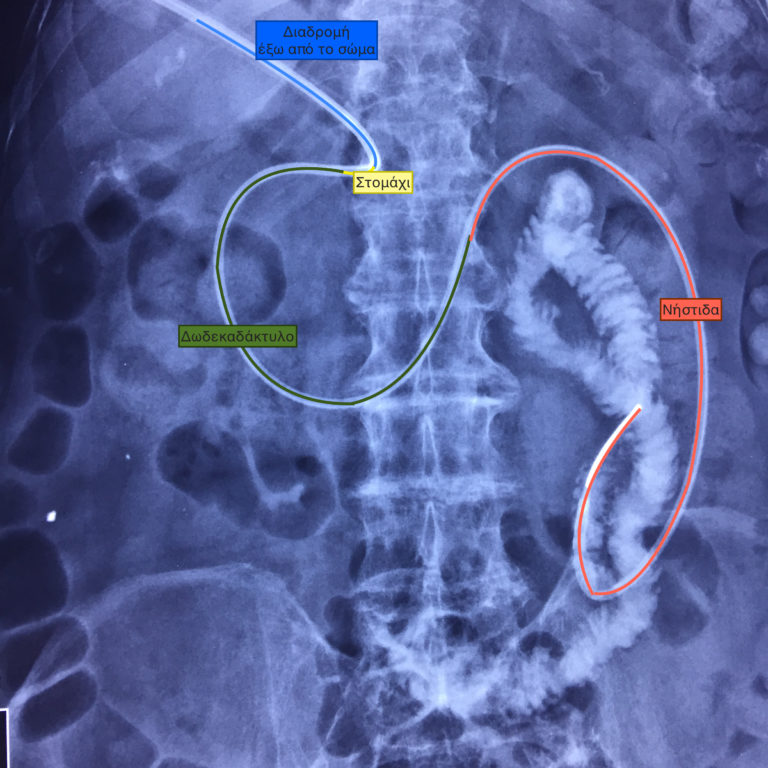

Η γαστροστομια με επέκταση στο έντερο, δηλαδή η εισαγωγή καθετήρα σίτισης μέσω γαστροστομιας στο λεπτό έντερο, είναι μέθοδος που αποτρέπει…

Δύο περιπτώσεις ενδοσκοπικής επανατοποθέτησης γαστρονηστιδικών σωλήνων, σε ηλικιωμένους ασθενείς που είχαν απλές γαστροστομιες και κινδύνευαν από επανειλημμένες εισροφήσεις τροφών, οι…